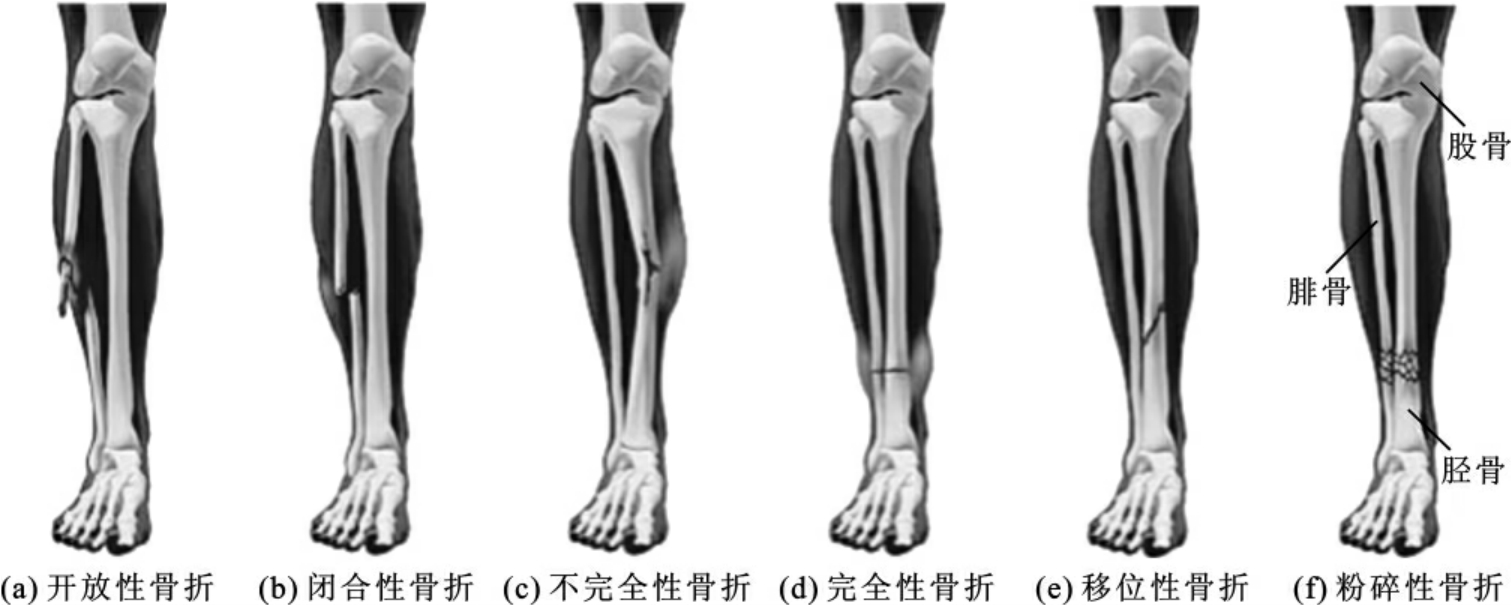

骨折有不同的分类方法,常见类型如图7-4-1所示。

图7-4-1 骨折的常见类型

1.按骨折是否和外界相通分类

骨折可分为开放性骨折和闭合性骨折。开放性骨折其附近的皮肤和黏膜破裂,骨折处与外界相通,此类骨折伤口及骨折断端受到污染;闭合性骨折的骨折处皮肤或黏膜完整,不与外界相通。此类骨折没有污染。

2.按骨折的程度分类

骨折可分为完全性骨折和不完全性骨折。完全性骨折骨的完整性或连续性全部中断,管状骨骨折后形成远、近两个或两个以上的骨折端;不完全性骨折骨的完整性或连续性仅有部分中断,如颅骨、肩胛骨及长骨的裂缝骨折,儿童的青枝骨折等。

3.按骨折稳定程度分类

骨折可分为稳定性骨折和不稳定性骨折。稳定性骨折的断端不易移位或复位后经适当的外固定不易发生再移位;不稳定性骨折的断端易移位或复位后易于发生再移位。

4.按骨折的形态分类

骨折可以分为横形骨折、斜形骨折、螺旋形骨折、移位性骨折、粉碎性骨折、压缩骨折、嵌入骨折等。